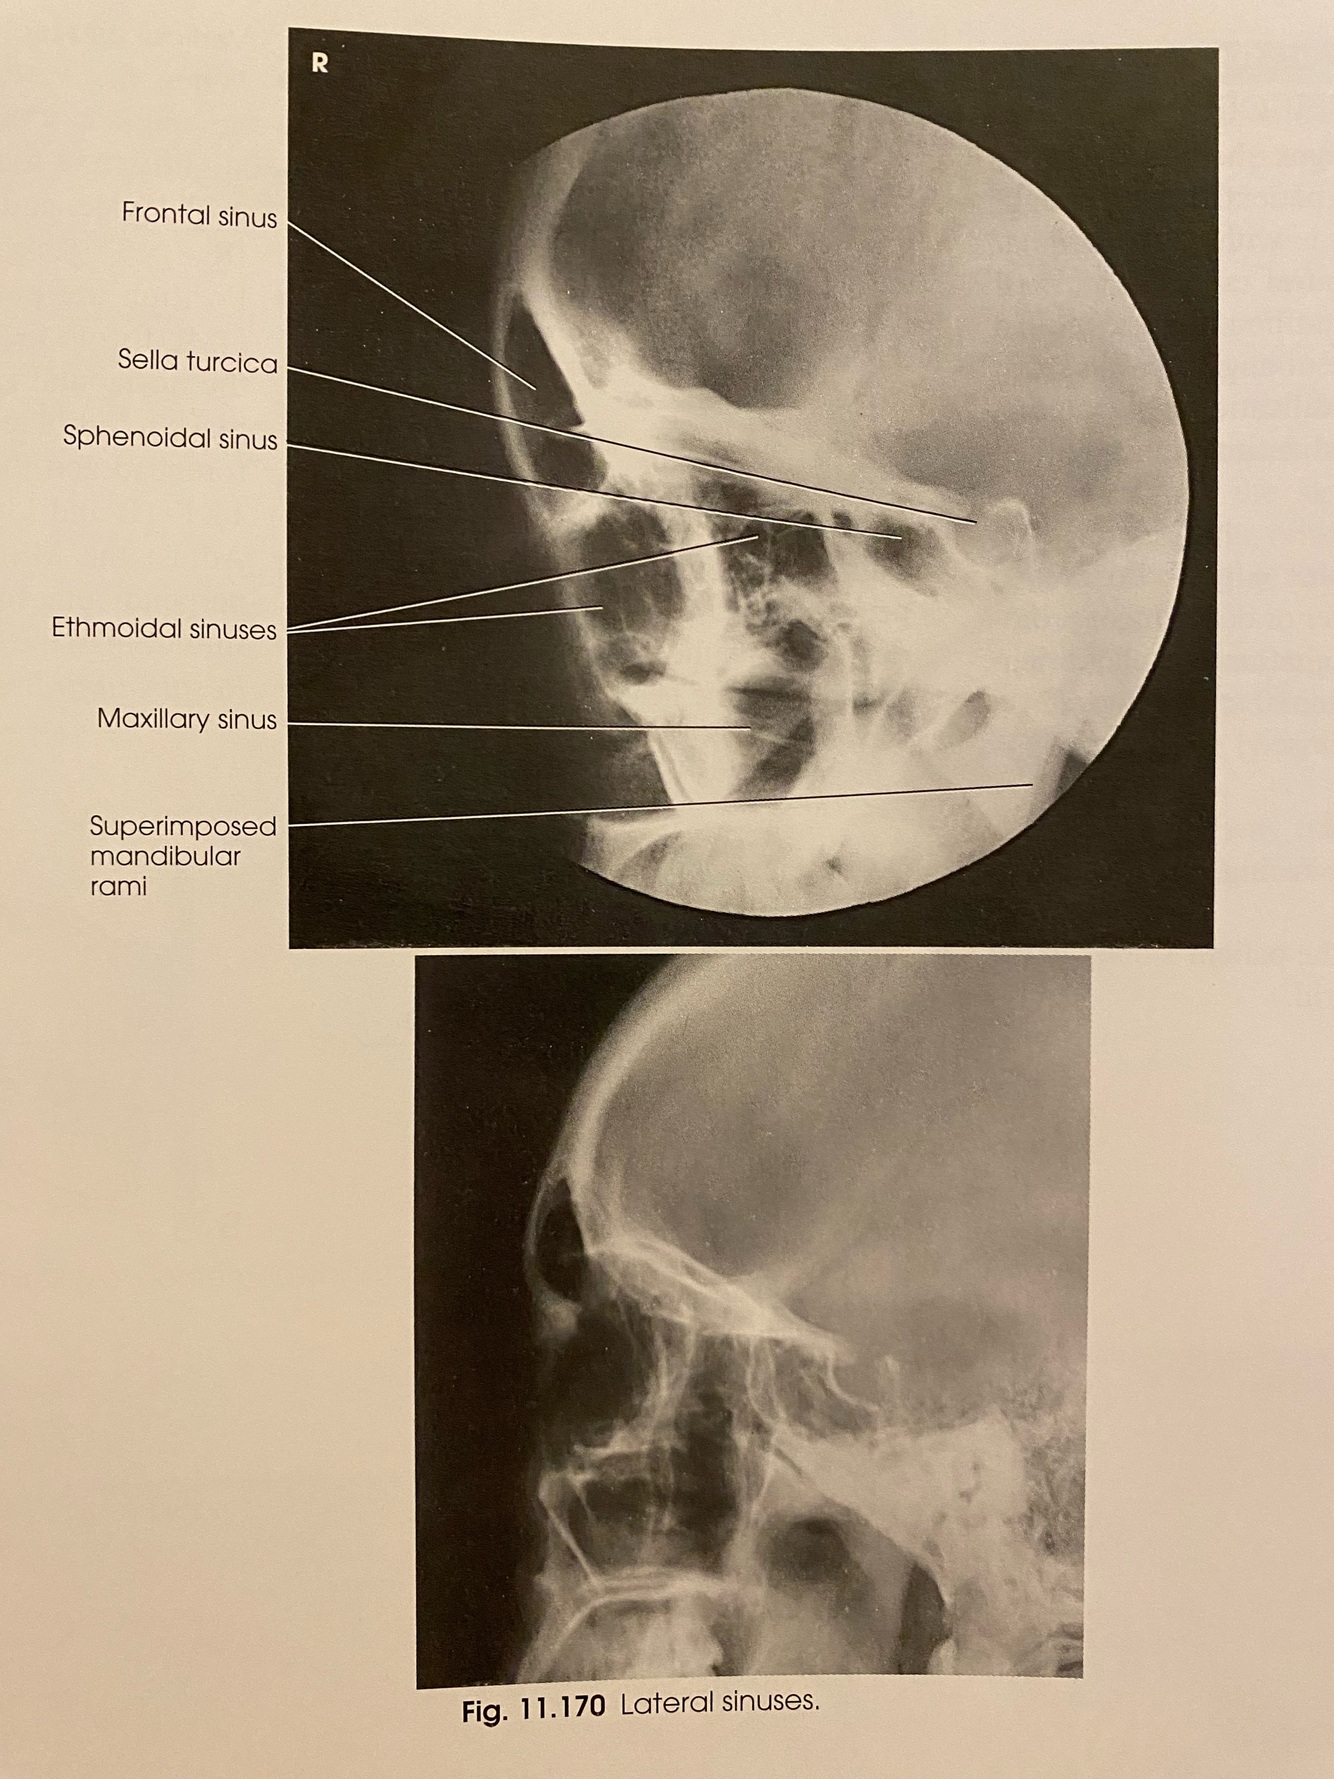

LATERAL Positioning

A

-MSP: II to IR

-IPL: ⟂ to IR

-IOML: II to long axis of IR (or ⟂ to front edge of IR)

-CR: 0.5-1” posterior to outer canthus

-SID: 40”

-Respiration: suspend

LATERAL Evaluation Criteria

-Proper Collimation

-All four sinus groups, best demonstration of sphenoid sinus

-No rotation or tilt

-SI orbital roofs

-SI mandibular rami

-Sella turcica in profile

-Brightness and contrast sufficient to visualize air fluid levels, if present